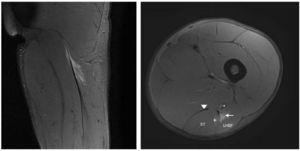

Nineteen years old professional football player suffered sudden pain in his posterior, upper part, thigh when sprinting and was unable to play. Clinical signs showed an acute ham-string strain (painful palpation, limited range of motion (ROM), decrease of strength, painful stretching and difficulty to walk normally). MRI was performed 24 h post-trauma with a 3-T scanner (Titan Vantage, Toshiba). LHBF injury and its characteristics are described in Figs. 1 and 2. The final diagnosis was a proximal MTJ injury of LHBF localized at 10 cm from the ischial tuberosity and 6 cm from the onset of the MTJ. The expected lay-off time was 7-8 weeks. The recovery treatment consisted basically in 3 stages: physiotherapy measures, strength and neuromuscular training in the gym and specific individual football training in the field.

Figure 2 Coronal and axial T2 Fat-saturated images of the left hamstring show thickening and signal intensity changes of the free tendon (arrow), blurring contours and discontinuity that extent until proximal MTJ. There is mild distal retraction of the proximal MTJ. Semitendinosus muscle belly (ST), gluteus maximus (GM), semimembranosus tendon (arrowhead) and sciatic nerve (*).